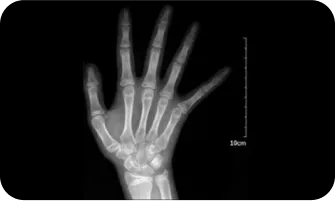

02

엑스레이 검사를 이용한

여아의 골연령검사

300점

400점

8.5세

500점

10세

600점

11세

700점

12세

800점

13 ~ 14세

900점

14 ~ 15세

1000점

15세 ~